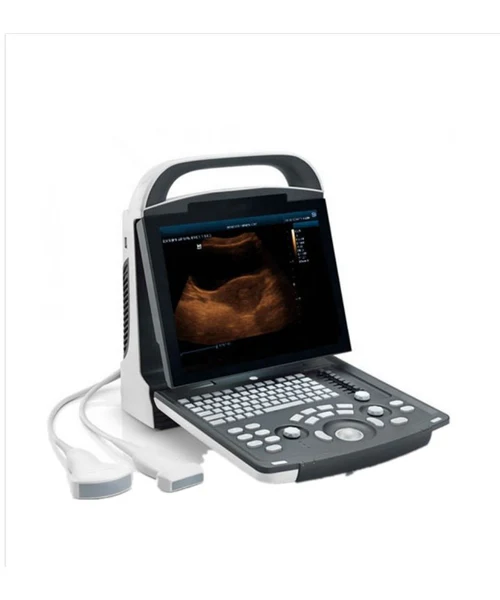

Mindray DP-10 Ultrasound Diagnostic UItrasound System for vet

Model: PSKU0060

1.Specifications:1)12.1”LED monitor with 30 degree tilt functionality2.User friendly control panel with backlit,silicon keyboard 3)Lightand compact design for extreme portability4)THI(Tissue HarmonicImaging)for enhanced contrast r...

1.Specifications:

1)12.1”LED monitor with 30 degree tilt functionality

2.User friendly control panel with backlit,silicon keyboard

3)Lightand compact design for extreme portability

4)THI(Tissue HarmonicImaging)for enhanced contrast resolution

5)8-TGCassuring accurate image control

6) IP(Image Processing)forfast image optimization

7)Abroad rangeof transducers for abdomen,obstetrics,gynecology,cardiology small parts,urology,vascular and nerve application

8)User-defined keys for personalized operations

9)One-key image/cine storage to localdiskor USB drive

10)Lithium-ion battery